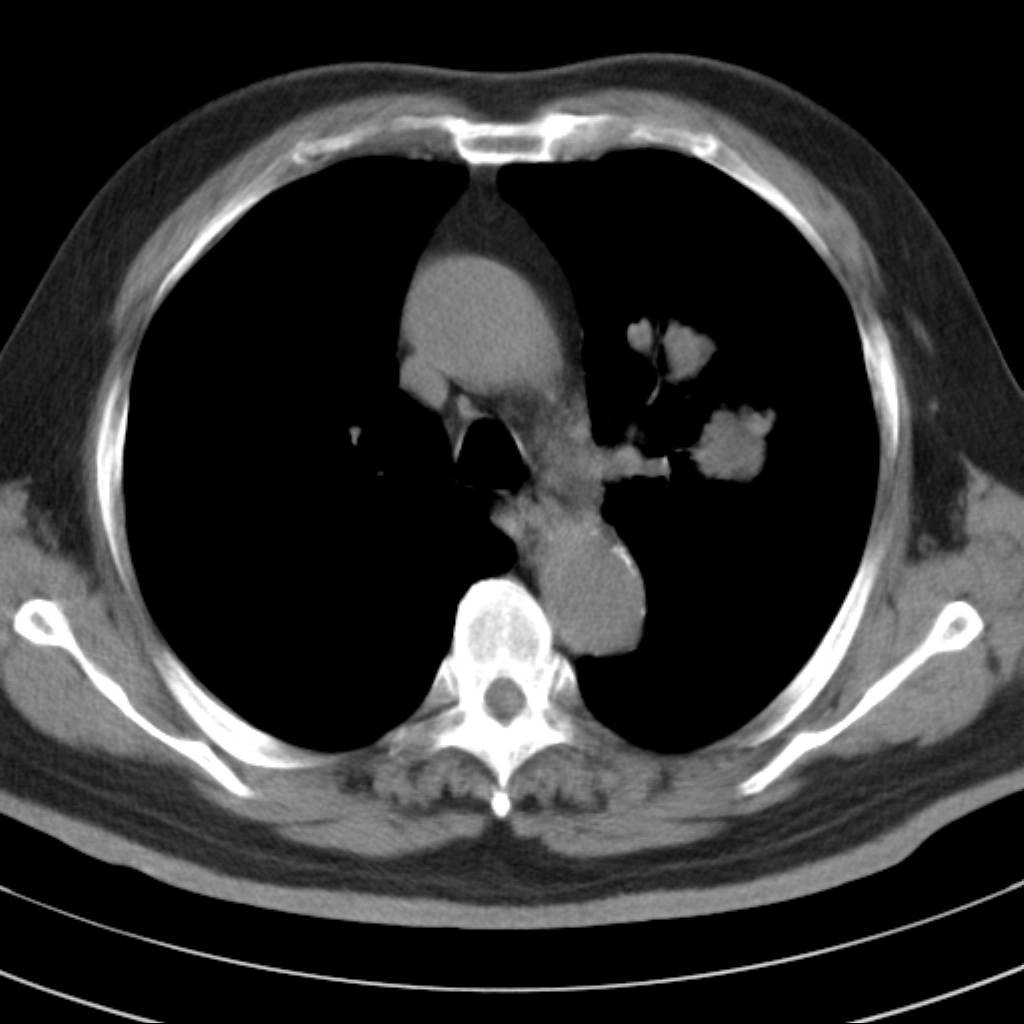

标题: CT18644:男,82岁,体检发现左肺阴影. [打印本页]

标题: CT18644:男,82岁,体检发现左肺阴影.

岁数太大,没有增强。麻烦见过的,给个诊断,顺便再说说病因

左侧中心型肺癌并粘液栓形成。很典型的。手套征。

支持 左肺上叶中央型肺癌并支气管内粘液栓形成。

支持考支气管扩张伴粘液栓,但导致粘粘液栓的病因有待进一步检查。支持左上叶支气管基部肿物,肺癌可能性大,但肿块似与肺动脉右支保持良好的伙伴关系,不除外为肺动脉扩张所致,建议增强。

左肺动静脉畸形,肺动静脉畸形(pavms)是肺血管发育异常,是肺动脉与肺静脉直接相通形成短路,通常包括一条供血动脉及一条或数条引流静脉,以及他们之间的异常血管团。约70%的患者伴发遗传性出血性毛细血管扩张症。 影像检查的目的在于确定病灶位置、大小、形态、数目。x线可表现为:1.结节型(直径小于3cm)2.团块型(直径大于3cm)3.弥漫型(肺内散在逗点状影),以团块状居多。 ct扫描可见单发或多发肺内结节,有的有蜿蜒迂曲的团块影,边缘光滑、锐利,增强ct扫描可见增粗、扭曲的血管影和/或类圆形的增粗的血管断面,甚至供血动脉及引流静脉。

平扫似avm,建议增强扫描。

考虑左肺上叶中央型肺癌并支气管内粘液栓形成。

支持 左肺上叶中央型肺癌并支气管内粘液栓形成,阻塞性肺炎

左肺上叶中央型肺癌